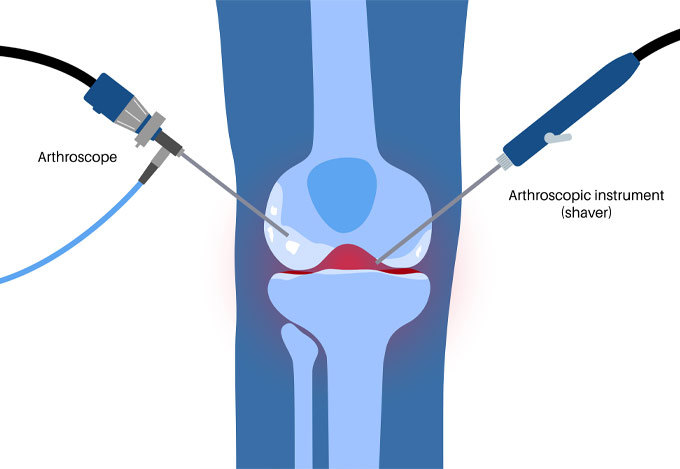

Κατά τη διάρκεια της εργασίας του στο Ηνωμένο Βασίλειο εκπαιδεύτηκε σε σύγχρονες τεχνικές Αρθροσκοπικής Χειρουργικής και Επανορθωτικής Χειρουργικής Ισχίου, Γόνατος και Ώμου. Επιπλέον έχει δώσει πολυάριθμες διαλέξεις και έχει εκπαιδεύσει νεότερους Ορθοπαιδικούς και φοιτητές Ιατρικής. Αξιοσημείωτο και πλούσιο είναι το επιστημονικό του έργο με συμμετοχή σε δεκάδες συνέδρια και σεμινάρια στην Ελλάδα και στο εξωτερικό και έχει πληθώρα προφορικών ανακοινώσεων και δημοσιεύσεων.